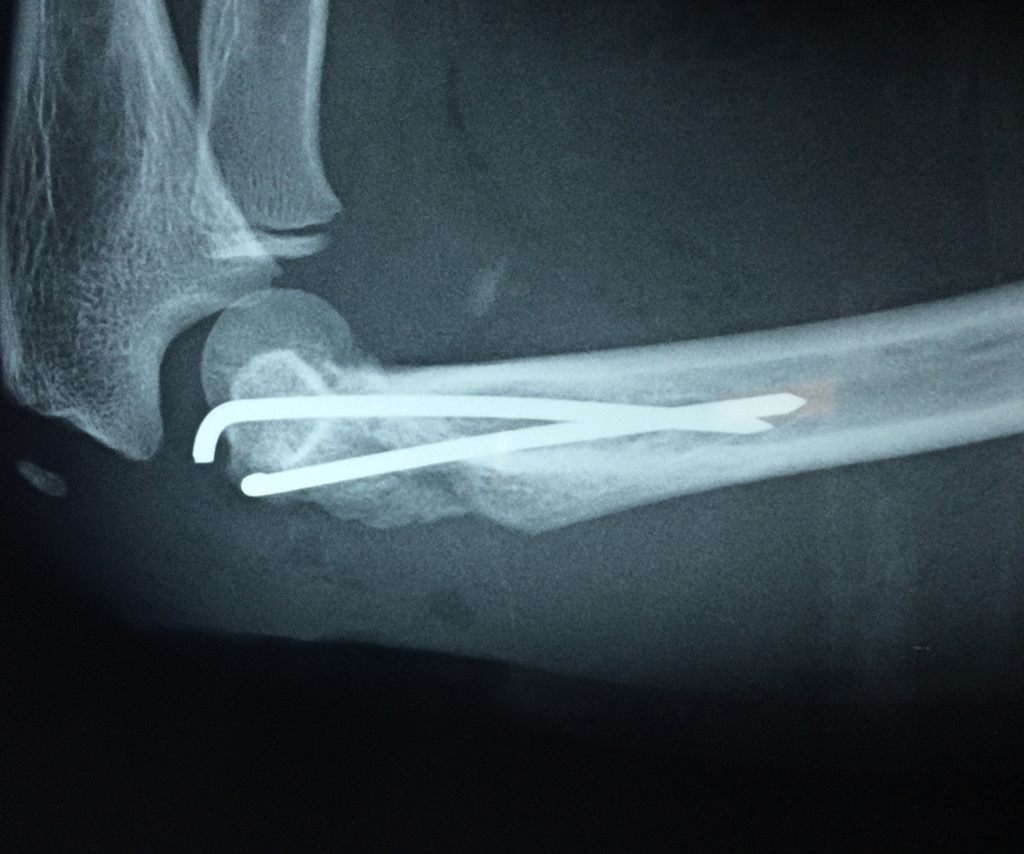

Los extremos óseos se conectan entre si por un conjunto de ligamentos que contribuyen a su fijación y están rodeado por una estructura común que se llama cápsula articular, en cuyo interior se encuentra el líquido sinovial.

En el lenguaje común se le da el nombre de codo a la parte posterior y prominente situada en la unión del brazo con el antebrazo.